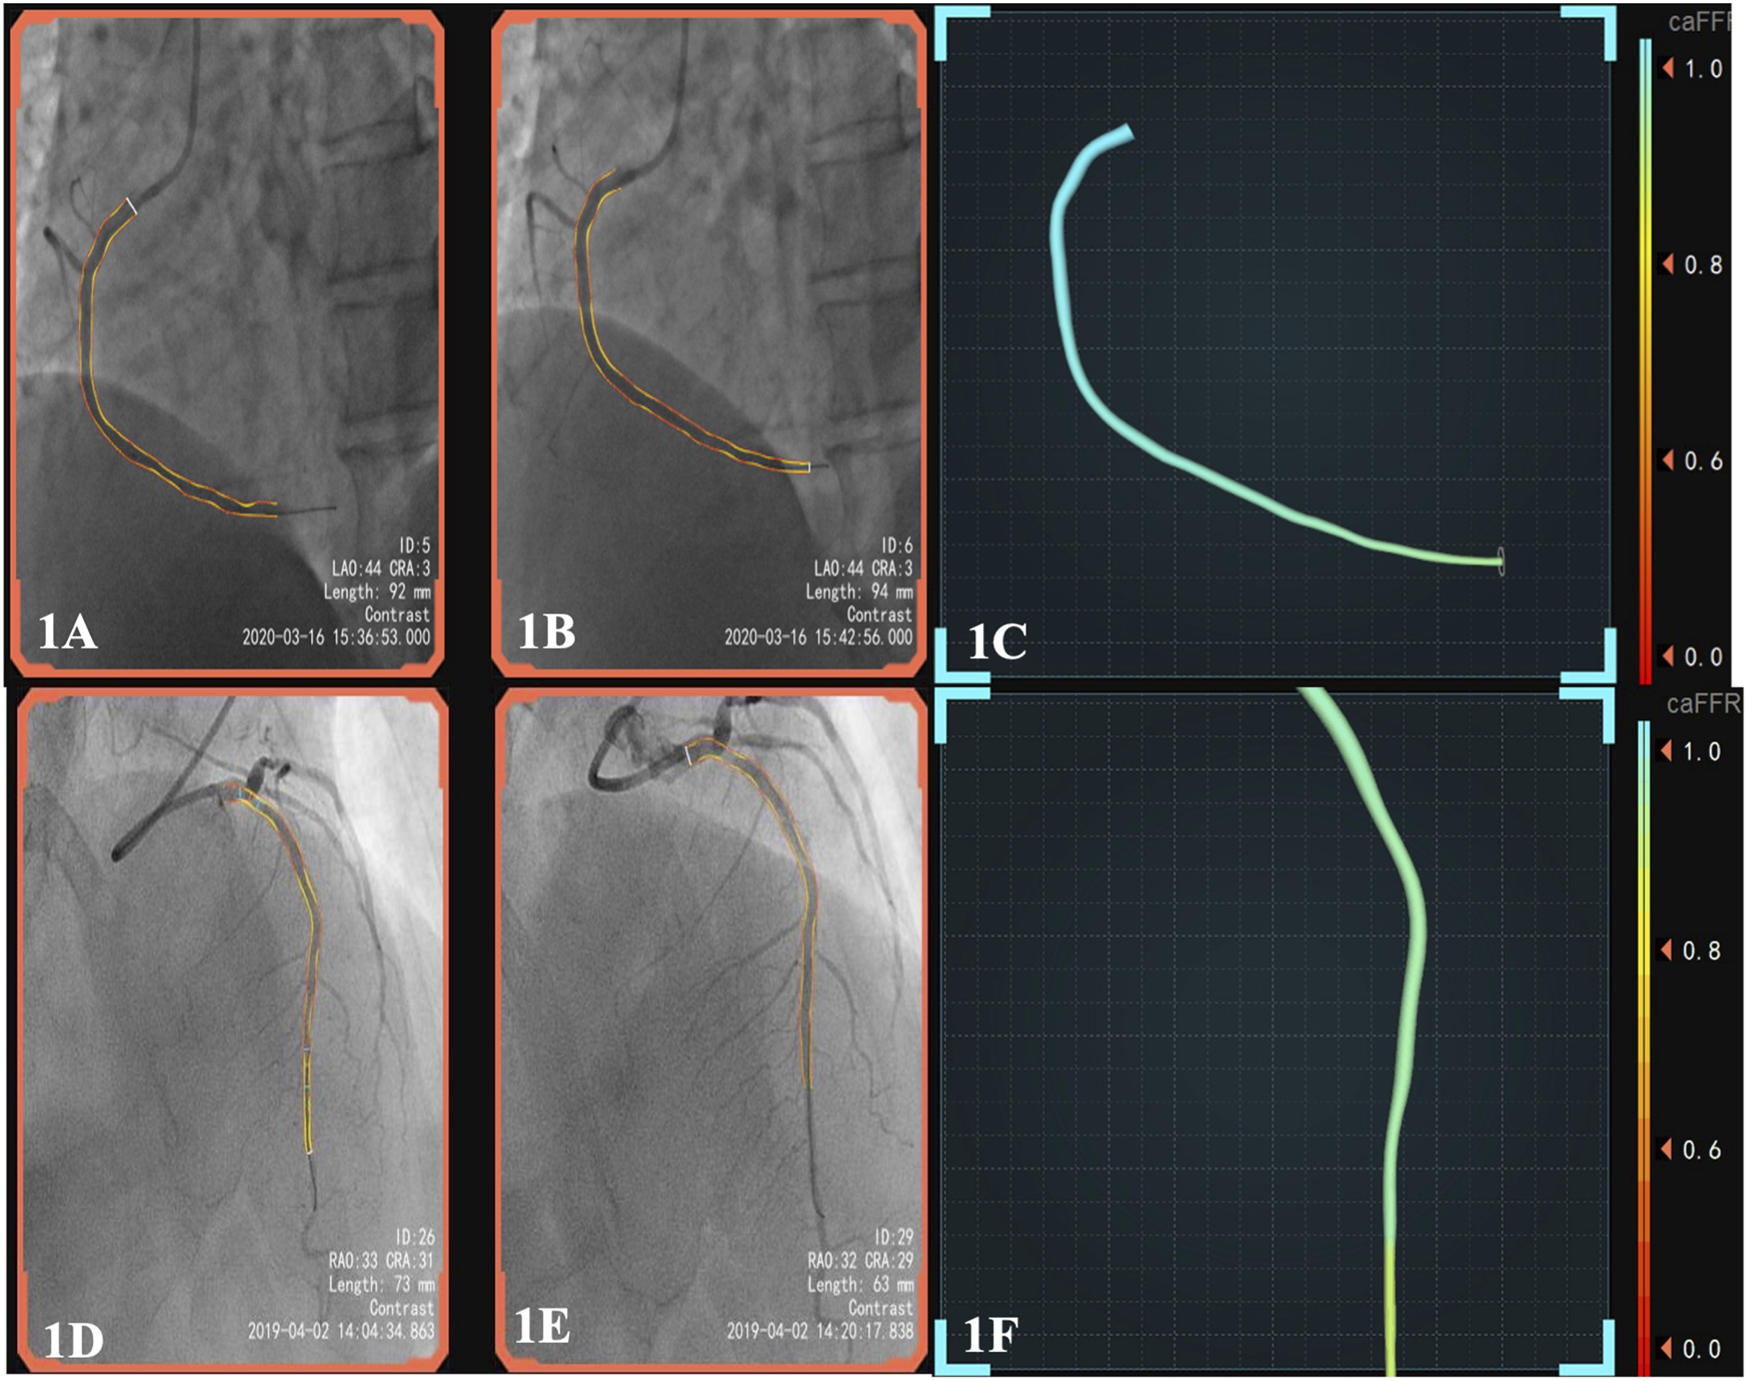

The CPFD-IMR measurement was conducted using the software (FlashAngio, Rainmed Ltd., Suzhou, China, Figure 1) as described before (Ai et al., 2020). In brief, a three-dimensional reconstruction of coronary arteries was firstly conducted for the target vessels, followed by the estimation of caIMR by CPFD with a validated method (Li et al., 2020).

FIGURE 1

(A), pre-surgery angiography; (B), post-surgery of DCB; (C), the patient’s post-operative caFFR was normal and caIMR was high (caFFR = 0.92, caIMR = 42.1). After 6 months of follow-up, the patient had myocardial infarction again.; (D), pre-surgery angiography; (E), post-surgery of DES; (F), the patient’s postoperative caFFR and caIMR (caFFR = 0.91, caIMR = 22.8) were normal and no MACEs events occurred in 1.5 years of follow-up. Abbreviations: caFFR, coronary angiography-derived fractional flow reserve; caIMR, coronary-angiography-derived index of microcirculatory resistance; DES, drug-eluting stents; DCB, drug-coated balloons; MACE, major adverse cardiovascular events.